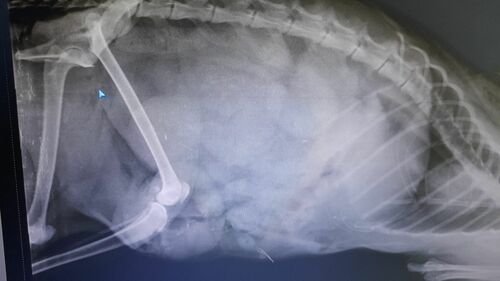

Minha gatinha Vênus nunca fugiu, quando escapou com medo da chuva, acabou indo para rua, e assim acabou sendo atacada por um cachorro, abrindo a barriga dela. O veterinário disse que causou uma hérnia, por conta da infecção. Sofri um acidente de trabalho, e tive queimaduras de 3° grau, que me fizeram ficar em casa por 13 dias, o que me fez perder prêmio de assinuidade na empresa

Cirurgia de hérnia R$ 800

Agora também ela passou por uma cesárea de emergência e ficou 4 semanas internadas, o que resultou em 3 mil reais 😭😭😭, na clinica SOS animais, em Brusque, Santa Catarina.